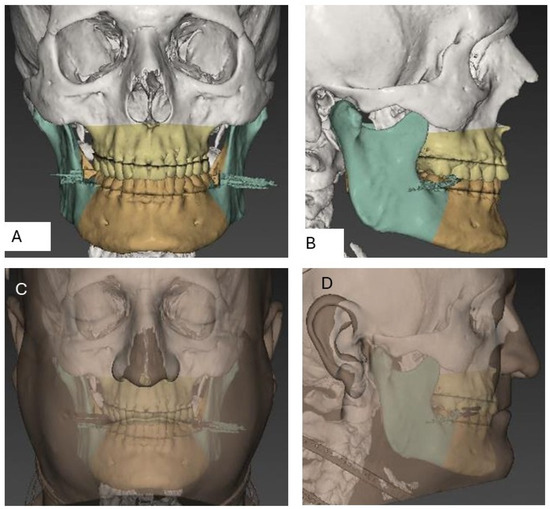

3.1.3. Cephalometric Changes Following Orthognathic Surgery

3.2.3. Cephalometric Changes Following Orthognathic Surgery